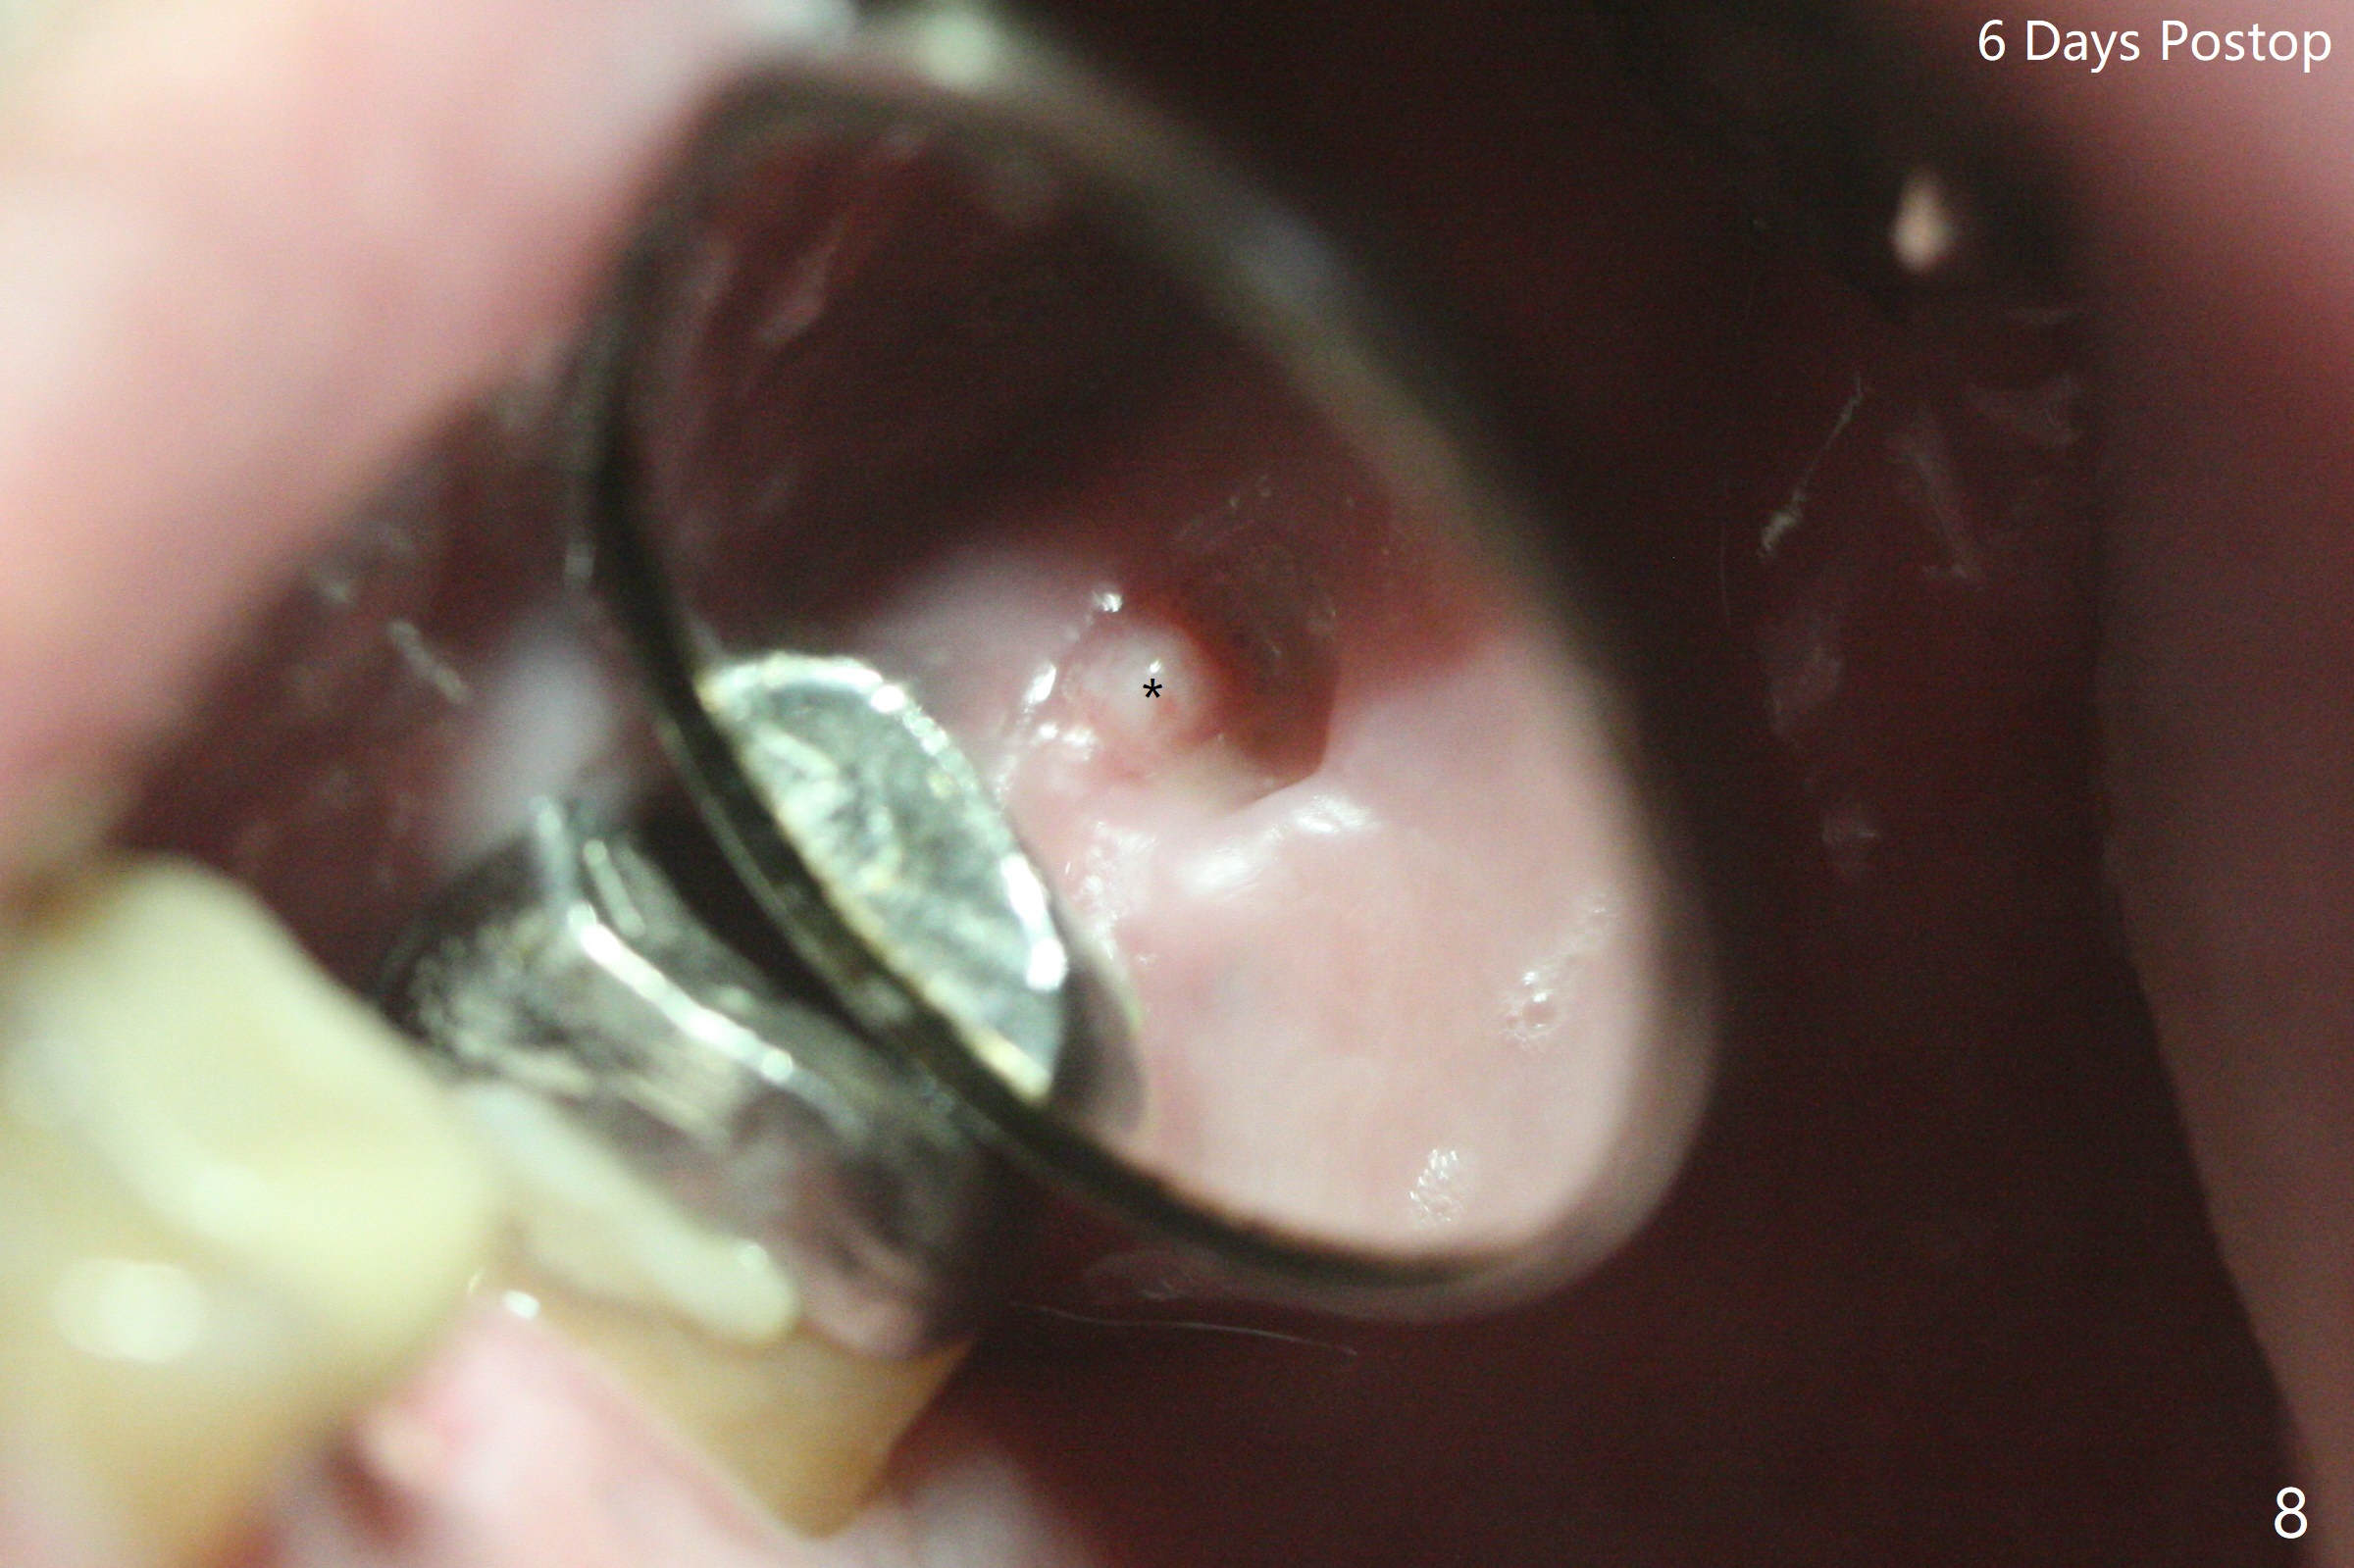

60岁男,左上6(牙根折裂严重骨质吸收)位点保存后6个月,回来植牙。术前CT显示骨质密度低,宽度足够,角化龈也宽,前后牙齿都有牙冠,制作导板麻烦,所以采纳徒手种植。使用4毫米活检打孔刀(Biopsy Punch)进入,简化手术,但是又怕开口不正,不敢用大号植体,术后CT发现钻洞偏颊侧。针对骨质密度低,使用1.2毫米钻头后(约8毫米),使用旋转式骨扩张器直至2.4/3.7毫米(图一(红虚线:原来骨质缺损)逐渐增加深度至11毫米),备洞几乎没有失去骨质,钻洞周围骨质密度谅必增高),取出最后一个扩大器后发现上颌窦底板破裂,放置粘性骨粉,使用4毫米报废植体做上颌窦提升,重复一次(图二,三),稳定性尚可。再次放置骨粉和PRF膜,使用正式植体提升(4.5x8毫米),临床上很难判断是否植体植入牙槽嵴之下(可能骨质疏松),只好拍摄CT(图四,五),好像正好牙槽嵴下,不过又植入骨粉一些(图七:*)。植体扭力~15Ncm,保险起见,放置愈合帽,表面放置少许骨粉以及打孔留下的牙龈(图六:G,之前一直泡在PRF上清液里),牙周胶水固定游离牙龈以及牙周敷料保护。术后6小时没有鼻出血。所以骨质缺损严重,植骨后,虽然缺损外形得到恢复,但是骨头质量,固定植体能力还不够。植牙时,需要适当改变手段,例如使用骨凿,提高骨质密度,而不是单纯使用钻头。术后病人恢复正常,没有疼痛,六天复诊,牙周敷料已经脱落,打孔的牙龈附着颊侧,部分骨粉暴露,但是看样子挺稳定,好像游离牙龈必须缝合。使用树脂敷料牢靠些。术后五周,伤口基本愈合,一处未愈合,与下面骨粉相通,用牙周探针稍微搅动,出血(图九)。擦干血迹,伤口还不错(图十)。术后2个月伤口好像正常愈合(图十一)。术后4.5个月根尖片显示6种植比5深,往后螺纹暴露可能性减少(图十二)。